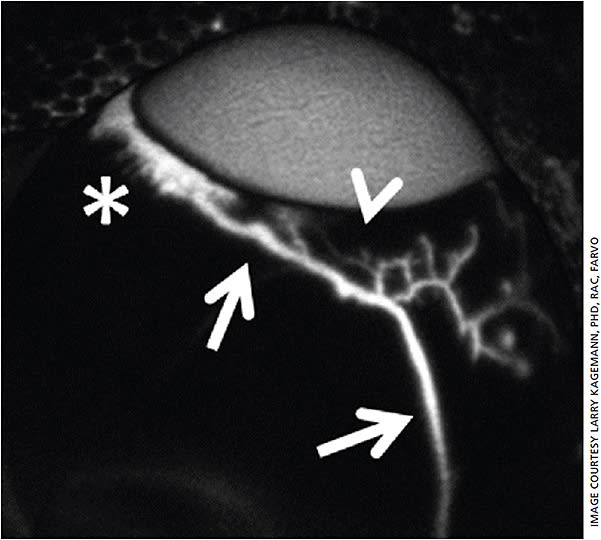

Utilizing advances in optical coherence tomography (OCT) imaging hardware and the sophistication of applied computer vision techniques to OCT imagery, we have demonstrated the ability to map the functioning aqueous humor outflow pathway in cadaveric and living eyes.2,13-15 Aqueous humor produces almost no signal within an OCT image. Thus, aqueous humor within the outflow vasculature creates a series of dark voids within the sclera. The black regions within the processed limbal OCT B-scan are comprised of aqueous humor displacing scleral tissue within the outflow vasculature and Schlemm’s canal (arrow). When a series of these scans is obtained through a volume of the limbus and image processing is used to display only the black regions (displayed as white in a black background), the living Schlemm’s canal (Figure 4) and distal vasculature (Figure 5) are visualized.2,13,15,16

Expanding the view to the entire OCT scan volume, the similarities between the living system and the casts created by Dr. Ashton become apparent. Since first published, the work has been repeated using newer swept-source OCT devices.3